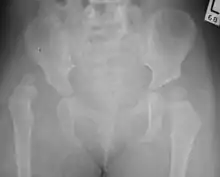

X-Ray Image showing hip dysplasia in a baby

Hip dysplasia can be diagnosed by ultrasound[42] and projectional radiography ("X-ray").[43] Ultrasound imaging is generally preferred at up to 4 months due to limited ossification of the femoral head up until then, and is the most accurate method for imaging of the hip during the first few months after birth. However, in most instances, ultrasound screening should not be performed before 3 to 4 weeks of age because of the normal physiologic laxity.[44][notes 1] When universal with targeted ultrasound screening was compared, the former results in an insignificant reduction in the late diagnosis of hip dysplasia, which is why universal ultrasonographic screening of newborn infants is not recommended by the American Academy of Pediatrics.[11]

Despite the widespread use of ultrasound, pelvis X-ray is still frequently used to diagnose or monitor hip dysplasia or for assessing other congenital conditions or bone tumors.[45]